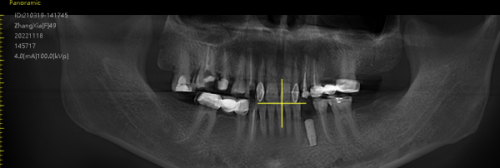

当您来到济南可恩口腔进行韩国neo种植牙时,会有一套规范的流程。首先,您需要进行全方面的口腔检查。医生会通过口腔X光片、CT等检查手段,了解您的牙槽骨密度、高度、宽度等情况,以及是否存在其他口腔疾病。然后,医生会根据检查结果,为您制定个性化的种植方案。这个方案会详细说明种植的时间、步骤、费用等信息。接下来,就是种植手术阶段。苗新海医生会在局部麻醉的情况下,将种植体植入牙槽骨内。手术过程中,医生会严格遵循无菌操作原则,确保手术的安心。术后,患者需要按照医生的嘱咐进行护理,包括服用消炎药、注意口腔卫生等。一般在种植体与牙槽骨结合稳定后,再进行牙冠的安装。整个过程可能需要几个月的时间,但在医生的专精指导下,患者可以顺利完成种植牙治疗。